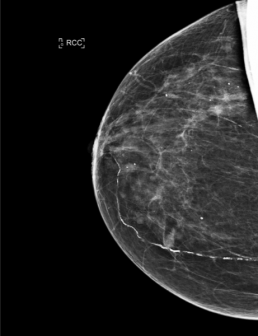

Case of the Week (week 38, 2022)

84-year-old patient, individual screening mammogram.

MammoScreen® points to an increased opacity with slightly irregular contours of the upper external quadrant of the right breast associated with polymorphic microcalcifications.

Ultrasound does not find a biopsy target, a macro biopsy is performed on microcalcifications and intra-ductal carcinoma.

*Case from Dr. Le Van An